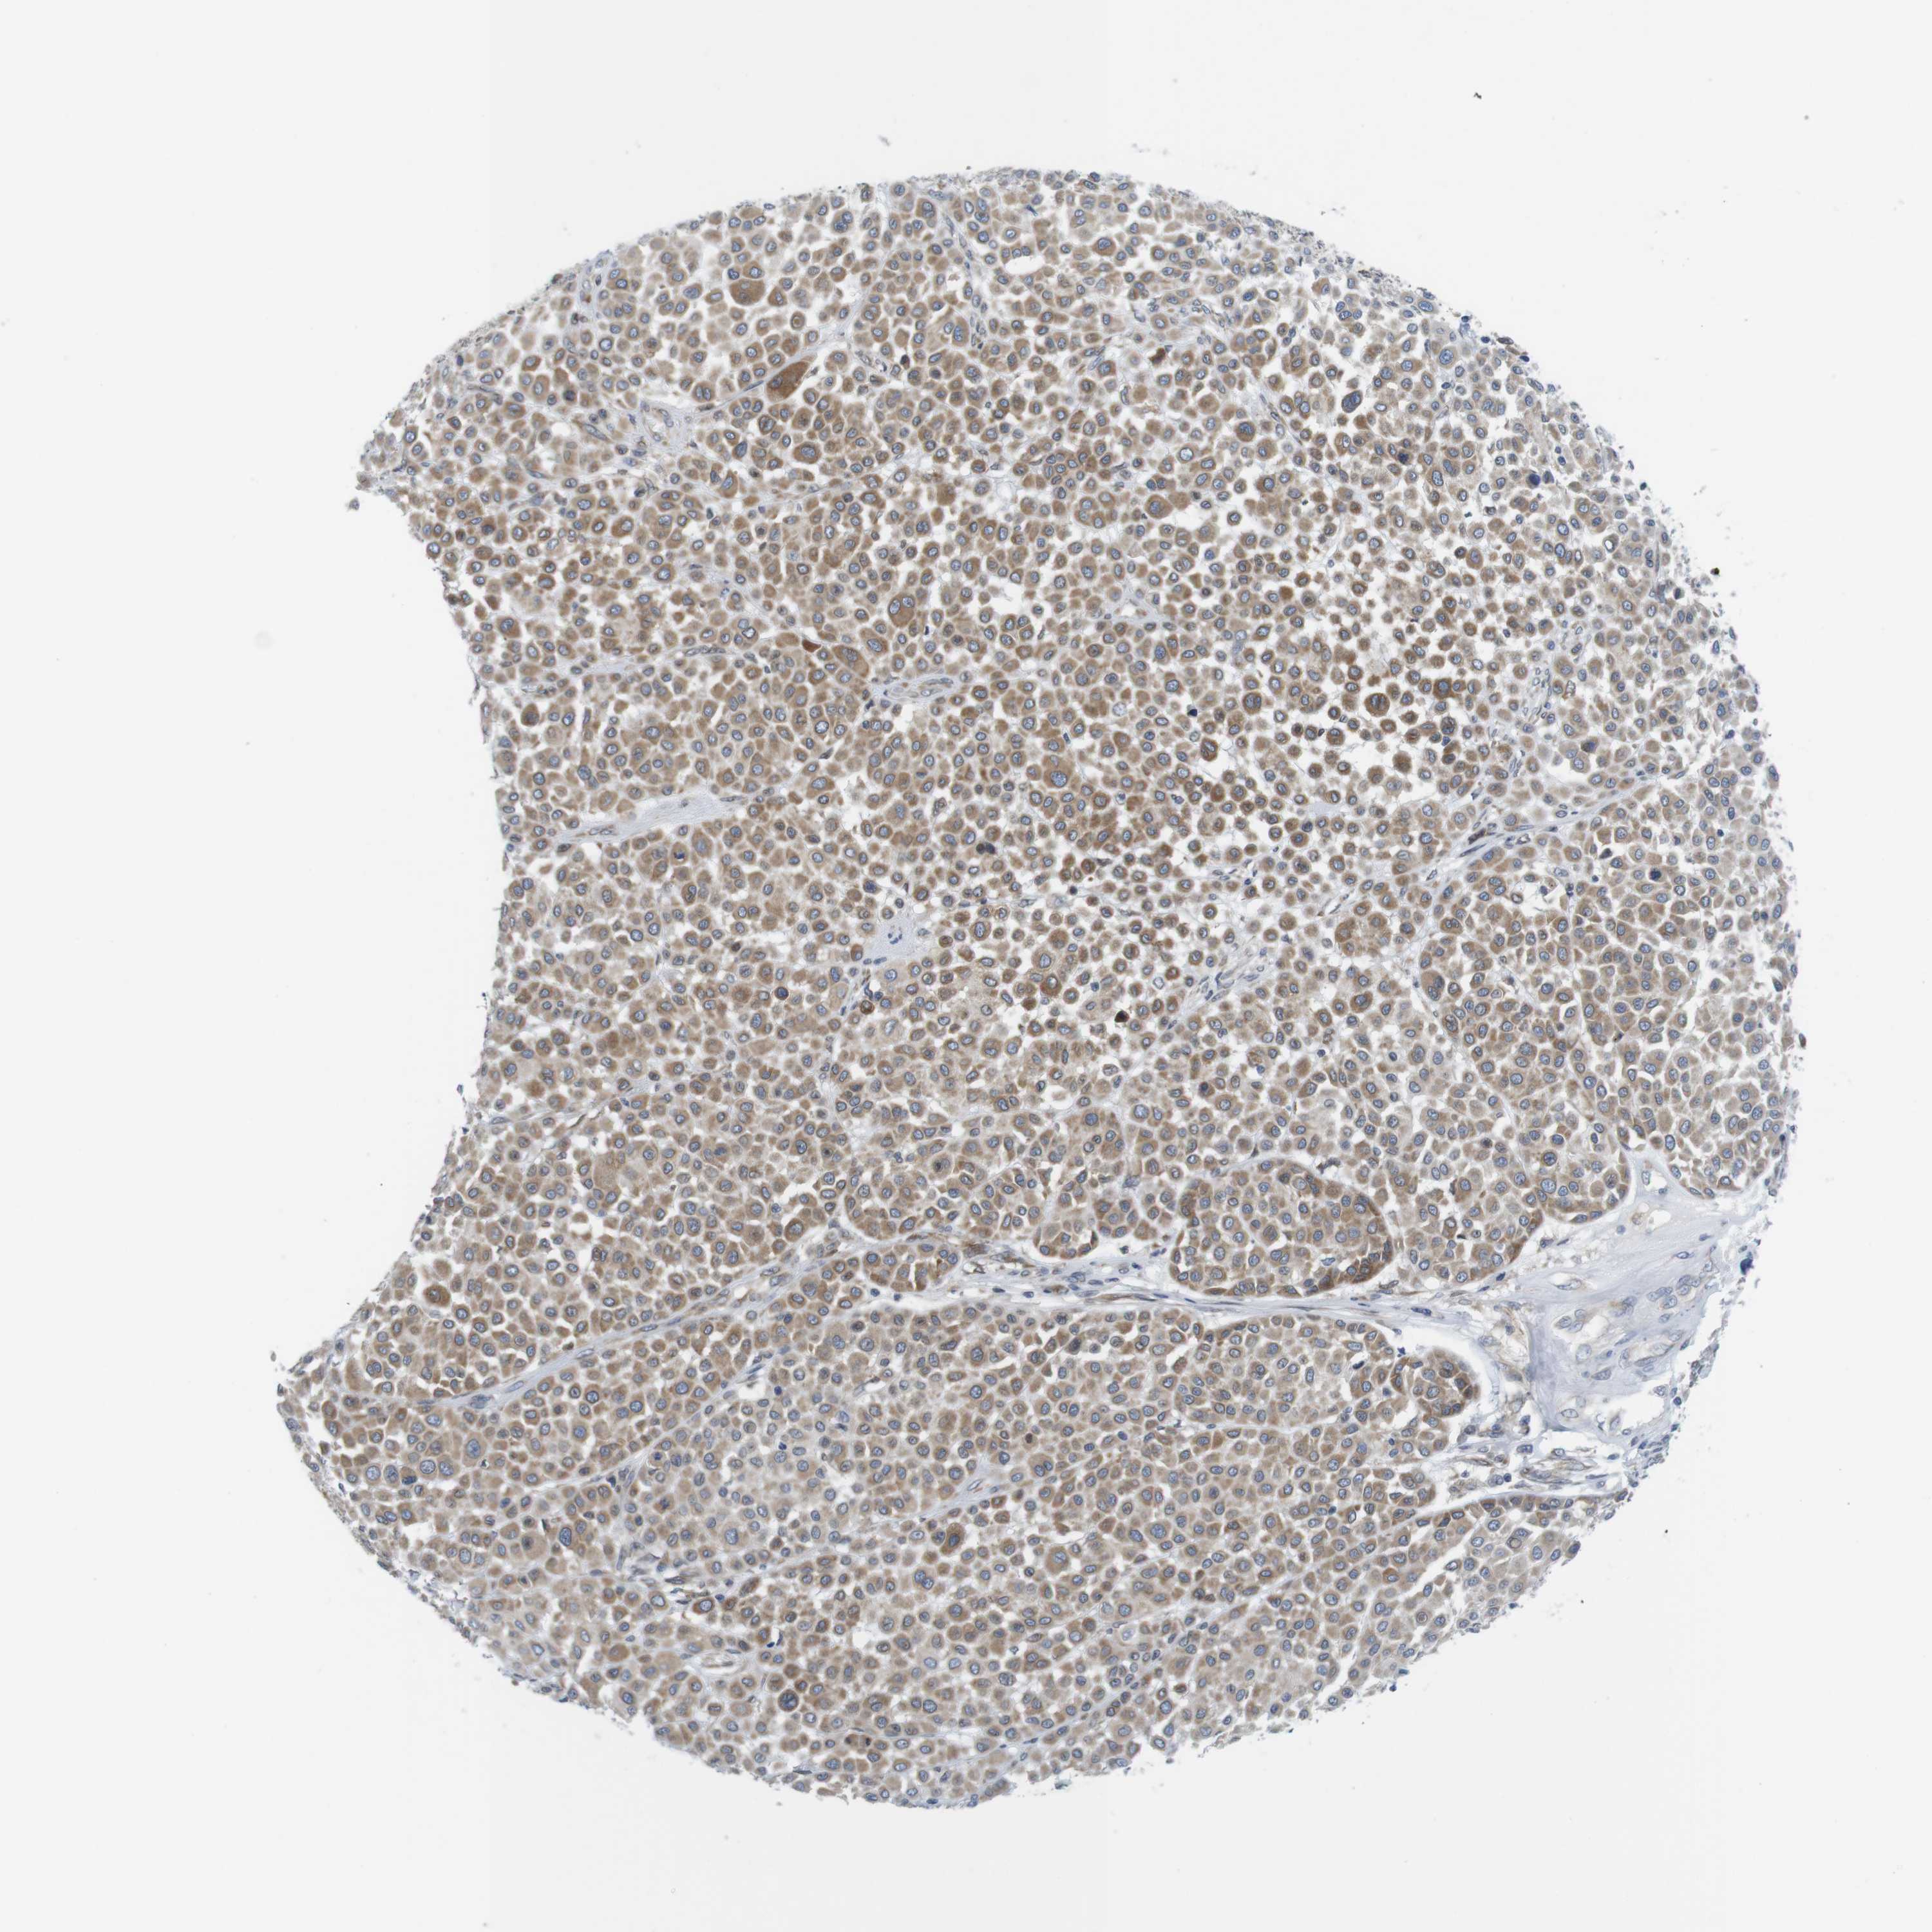

MELANOMA - Protein expressioni

A mouse-over function shows sample information and annotation data. Click on an image to view it in a full screen mode. Samples can be filtered based on level of antibody staining by selecting one or several of the following categories: high, medium, low and not detected. The assay and annotation is described here.

Note that samples used for immunohistochemistry by the Human Protein Atlas do not correspond to samples in the TCGA dataset.

Antibody stainingi

Antibody staining in the annotated cell types in the current human tissue is reported as not detected, low, medium, or high, based on conventional immunohistochemistry profiling in selected tissues. This score is based on the combination of the staining intensity and fraction of stained cells.

Each image is clickable and will lead to virtual microscopy that enables deeper exploration of all samples and also displays staining intensity scores, fraction scores and subcellular localization as well as patient and tissue information for each sample.

Antibody HPA015242

Antibody HPA015968

Staining

High

Medium

Low

Not detected

Intensity

Strong

Moderate

Weak

Negative

Quantity

>75%

75%-25%

<25%

None

Location

Nuclear

Cytoplasmic/membranous

Cytoplasmic/membranous,nuclear

Malignant melanoma, NOS

Malignant melanoma, Metastatic site